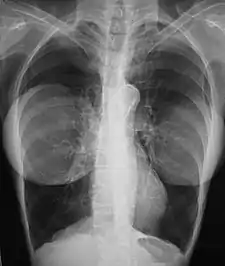

Mammography

The presence of radiologically opaque breast implants (either saline or silicone) might interfere with the radiographic sensitivity of the mammograph, that is, the image might not show any tumor(s) present. In this case, an Eklund view mammogram is required to ascertain either the presence or the absence of a cancerous tumor, wherein the breast implant is manually displaced against the chest wall and the breast is pulled forward, so that the mammograph can visualize a greater volume of the internal tissues; nonetheless, approximately one-third of the breast tissue remains inadequately visualized, resulting in an increased incidence of mammograms with false-negative results.[105][106]

The breast cancer studies Cancer in the Augmented Breast: Diagnosis and Prognosis (1993) and Breast Cancer after Augmentation Mammoplasty (2001) of women with breast implant prostheses reported no significant differences in disease-stage at the time of the diagnosis of cancer; prognoses are similar in both groups of women, with augmented patients at a lower risk for subsequent cancer recurrence or death.[107][108] Conversely, the use of implants for breast reconstruction after breast cancer mastectomy appears to have no negative effect upon the incidence of cancer-related death.[109] That patients with breast implants are more often diagnosed with palpable—but not larger—tumors indicates that equal-sized tumors might be more readily palpated in augmented patients, which might compensate for the impaired mammogram images.[110] The ready palpability of the breast-cancer tumor(s) is consequent to breast tissue thinning by compression, innately in smaller breasts a priori (because they have lesser tissue volumes), and that the implant serves as a radio-opaque base against which a cancerous tumor can be differentiated.[111]